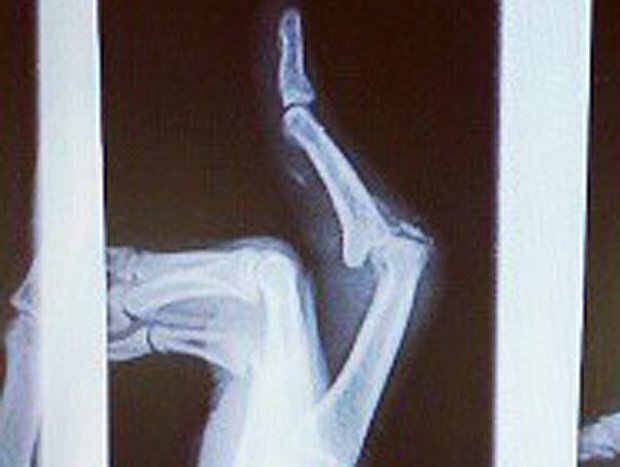

IN THE LATEST reminder that the injuries athletes play through are much more painful than they sound, Atlanta Falcons defensive back Thomas DeCoud revealed that he played two playoff games with a badly injured finger.

He tweeted out this X-ray with the caption, “Been playing with my finger like this since we played Tampa at home…Surgery tomorrow…wish ya boy luck ha.”

We’re not medical doctors, but this looks either dislocated or straight-up broken: